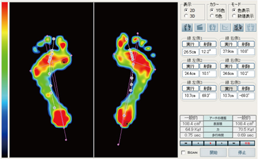

静止立位検査

プレートに両足肩幅で乗り、足底圧力の分布状態を検査をします。

検査時間内の平均圧力データを静止画として表示します。

基本画面

圧力分布の色分け表示や前後左右バランスを%表示します。

接地状態を分析しアーチの種類の確認も行えます。

バランス表示

前後・左右のバランスを数値化して表示します。

数値表示

色分けされた圧力分布を更に数値化します。(1~9段階)